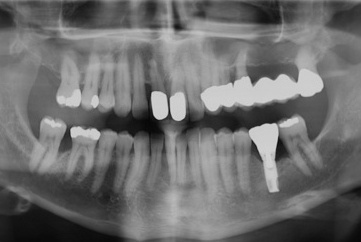

Der Erstbefund vom 20.08.1998 zeigte eine lokalisiert entzündliche marginale Gingiva mit Blutungsneigung auf Sondierung (SBI 32 %) vorrangig in regio 17, 11, 21, 24, 27, 36, 37, 41, 46. Austritt von Pus aus der Tasche an 22. Die Sondiertiefen waren durchweg erhöht, an einzelnen Parodontien konnten bis zu 12 mm sondiert werden (s. Abb. 12). Generalisiert weiche Beläge (API 46 %), harte Beläge in der UK-Front. An 41 singuläre parodontale Rezession und Zahnlockerung des Grades II, hier auch sehr schmale keratinisierte Gingiva. Mobilitätstest und Blanchingtest positiv. Der Röntgenbefund der Panoramaschichtaufnahme vom 11.08.1999 (s. Abb. 13) zeigt einen generalisierten horizontalen Knochenabbau mit vertikalen Einbrüchen in regio 17, 24, 25, 26, 36, 41 und 47. Wurzelfüllung an 36. Konkremente sichtbar. 18 elongiert. 38 und 48 halbretiniert mit Aufhellung distal.

a) Initialbehandlung vom 20.08. – 16.12.1999:

Gemäß den Vorgaben der systematischen Parodontalbehandlung wurden zunächst mehrfache professionelle Zahnreinigungen mit Anleitung des Patienten zu einer effizienten häuslichen Mundhygiene durchgeführt. Im Anschluss daran wurden die erkrankten Parodontien einem subgingivalen Scaling/Rootplaning unterzogen. Die Zähne 26 und 36 wurden als nicht erhaltungswürdig beurteilt und entfernt.

Aufgrund der fortgeschrittenen parodontalen Destruktion mussten die Zähne 26, 27 und 36 als nicht erhaltungswürdig beurteilt werden. Zur Herstellung einer kaufunktionell und ästhetisch befriedigenden Situation wurde die Anfertigung eines festsitzenden Zahnersatzes zur Versorgung der Schaltlücke 26/27 angestrebt. Da ein definitiver Zahnersatz erst nach einer ausreichend langen Reevaluationsphase angefertigt werden sollte, wurde zunächst ein metallverstärktes laborgefertigtes Langzeitprovisoriums von 23 auf 28 im August 2000 eingegliedert (s. Abb. 14). Für die Schaltlücke 36 war zu einem späteren Zeitpunkt eine implantatprothetische Versorgung vorgesehen.